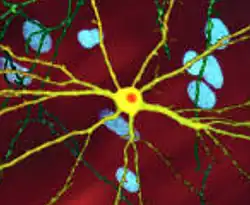

![]() | |

| An edited microscopic image of a medium spiny neuron (yellow) with an inclusion body (orange), which occurs as part of the disease process (image width 360 μm) | |

The toxic action of mHtt may manifest and produce the HD pathology through multiple cellular changes.[52][53] In its mutant (polyglutamine expanded) form, the protein is more prone to cleavage that creates shorter fragments containing the polyglutamine expansion.[52] These protein fragments have a propensity to undergo misfolding and aggregation, yielding fibrillar aggregates in which non-native polyglutamine β-strands from multiple proteins are bonded together by hydrogen bonds.[15] These aggregates share the same fundamental cross-beta amyloid architecture seen in other protein deposition diseases.[54] Over time, the aggregates accumulate to form inclusion bodies within cells, ultimately interfering with neuronal function.[15][52] Inclusion bodies have been found in both the cell nucleus and cytoplasm.[52] Inclusion bodies in cells of the brain are one of the earliest pathological changes, and some experiments have found that they can be toxic for the cell, but other experiments have shown that they may form as part of the body's defense mechanism and help protect cells.[52]

A somatic expansion of CAG repeats is involved in the progression of the disease. Over decades, the HTT gene first sees its CAG repeats expand to about 80 copies: the 35+ CAG locus causes additional slippage errors that expand the repeat. Then the process accelerates, reaching 150 copies within years. There is no significant toxic effect on the cell until 150 copies, at which point a large number of genes become progressively dysregulated. Over months, the medium spiny neuron slowly loses its cell identity until cell death pathways are activated.[57]